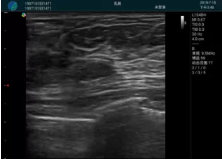

清晰顯示腺體內低回聲快影,邊界清晰,包膜較光滑

確定進針路徑并實時監(jiān)測抽吸針與腫塊位置關系

抽吸針進入腫塊內部進行旋切

抽吸過程中可見腫塊明顯縮小,并根據腫塊位置改變針道位置

抽吸旋切后再進行超聲復查,原腫塊區(qū)域未見殘留組織及出血